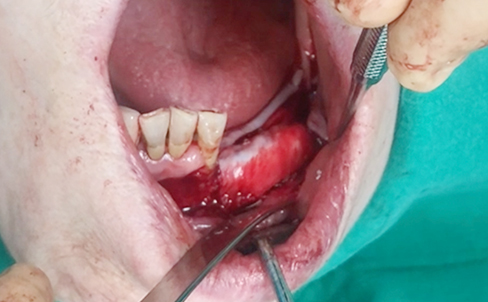

Simultaneous bone graft and implant placement